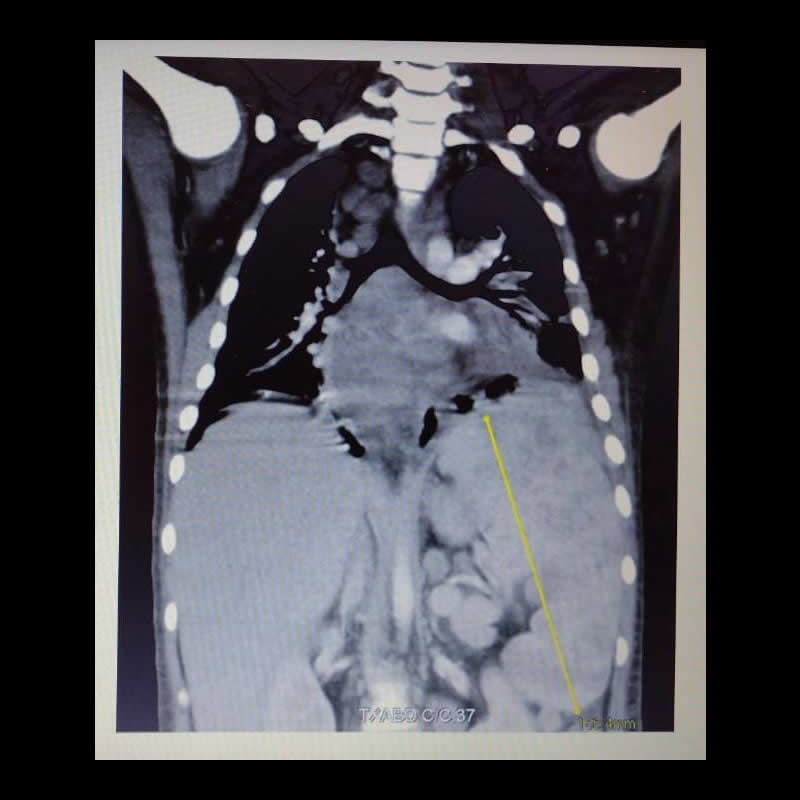

Paciente de 11 años. Alteración de sensorio.